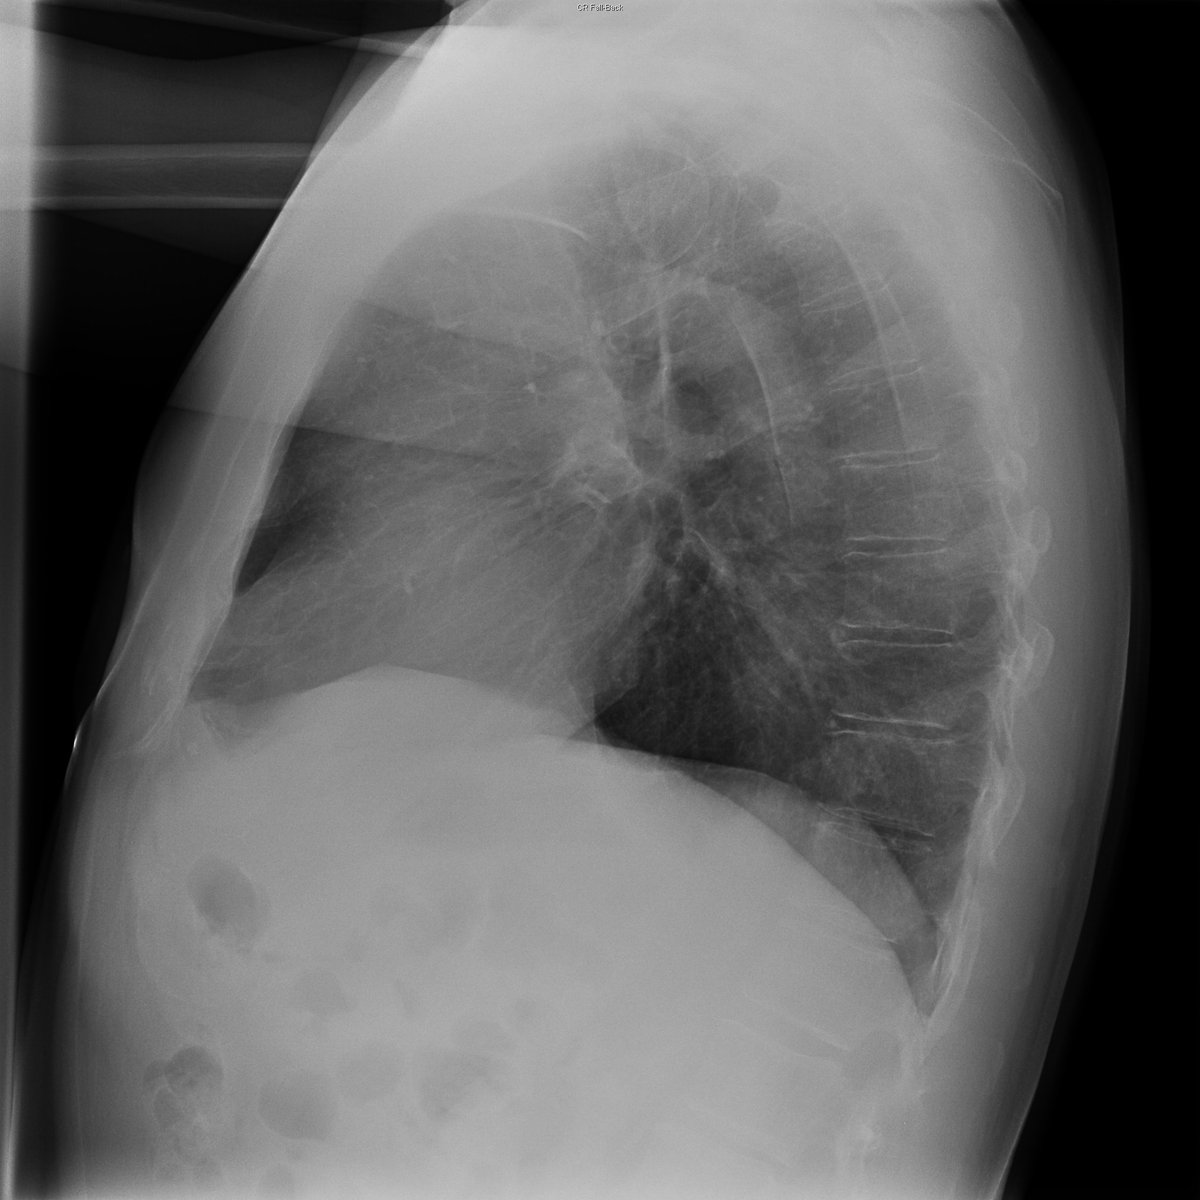

Case 47. 54yo male. Cough and fever. Day 1, 5 (acute respiratory failure), 7 and 9. Small peripheral opacities with progresion toward extensive bilateral consolidation.